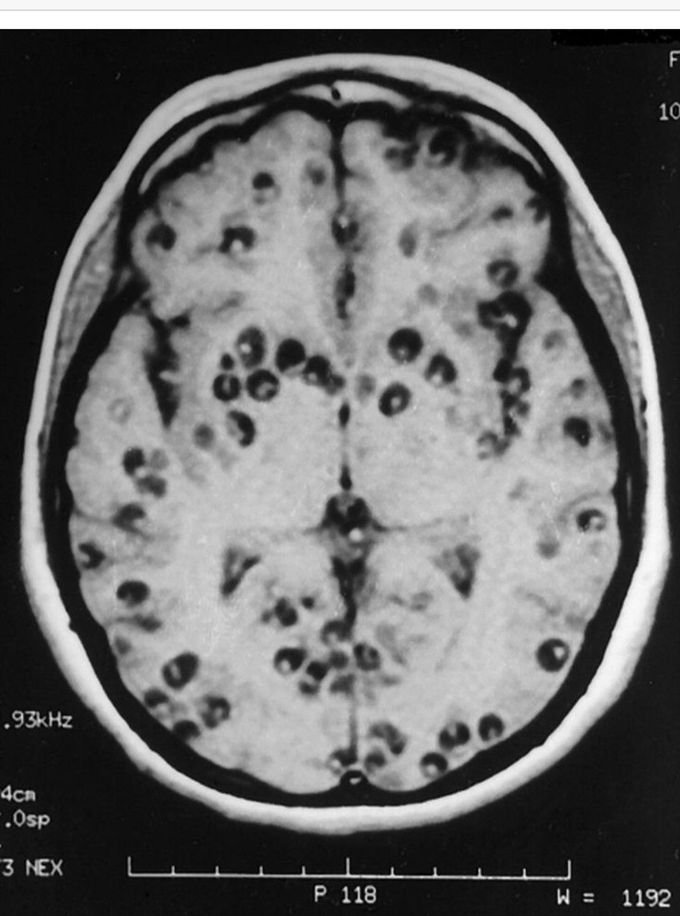

Cysticercosis

This MRI image shows the brain of a patient suffering from Neurocysticercosis. Each dark round spot is an encysted Taenia solium larva.